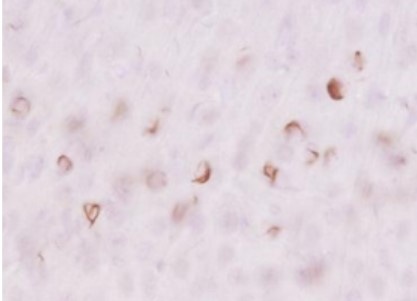

免疫組織染色

+

ビオチン標識二次抗体

ABC法

| 動物種 | マウス (6ヶ月齢、野生型、凝集α-シヌクレインを脳内に注入) |

| 部位 | 線条体 |

| サンプル | 50 µm厚 ビブラトーム切片 |

| 抗体濃度 | 1:1,000 |

| 染色法 | DAB染色 |

<データ提供>

東京大学大学院 医学系研究科 桑原先生、岩坪先生

[結果]

ビオチン標識抗体とABC法を組み合わせることで、二次抗体を用いた場合よりもバックグラウンドが抑えられ、明瞭に染色できた。